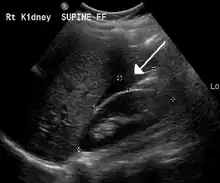

Blood in Morrison's pouch between the liver and kidney due to a ruptured ectopic pregnancy

The most common complication is rupture with internal bleeding which may lead to hypovolemic shock. Damage to the fallopian tubes can lead to difficulty becoming pregnant in the future. The woman's other fallopian tube may function sufficiently for pregnancy. After the removal of one damaged fallopian tube, pregnancy remains possible in the future. If both are removed, in-vitro fertilization remains an option for women hoping to become pregnant.[10][11][12]